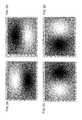

FIGS. 2A-D are edge detection filters.FIG. 2A is an outer edge filter that detects high (top) to low (bottom) horizontal edges.FIG. 2B is an inner edge filter that detects low (top) to high (bottom) horizontal edges.FIG. 2C is a left edge filter that detects high (left) to low (right) vertical edges.FIG. 2D is a right edge filter that detects low (left) to high (right) vertical edges.

In various embodiments, calcified regions are detected automatically by processing OCT images with edge detection filters.FIGS. 2A-D show four exemplary edge detection filters. Each filter detects a different boundary direction. In one embodiment, the edge detection filters include a top bottom filter, a bottom top filter, a right left filter and a left right filter. Other directional orientations indicating a transition from a first direction to a second direction can be use without limitation. Intensity changes such as from low to high can also be use to categorize the filters or otherwise specify their respective filter responses. In one embodiment, these directional edge detectors give maximum response or a relative extrema response in regions where the edge lines up with the direction of the ridge.

FIG. 2A is an outer edge filter that detects high (top) to low (bottom) horizontal edges. The outer edge filter could also be referred to as a top edge filter because polar space OCT images typically orient the endothelium at the top of the image.FIG. 2B is an inner edge filter that detects low (top) to high (bottom) horizontal edges. The inner edge filter could also be referred to as a bottom edge filter because polar space OCT images typically orient the intima tissue layer at the bottom of the image.FIG. 2C is a left edge filter that detects high (left) to low (right) vertical edges.FIG. 2D is a right edge filter that detects a low (left) to high (right) vertical edge.